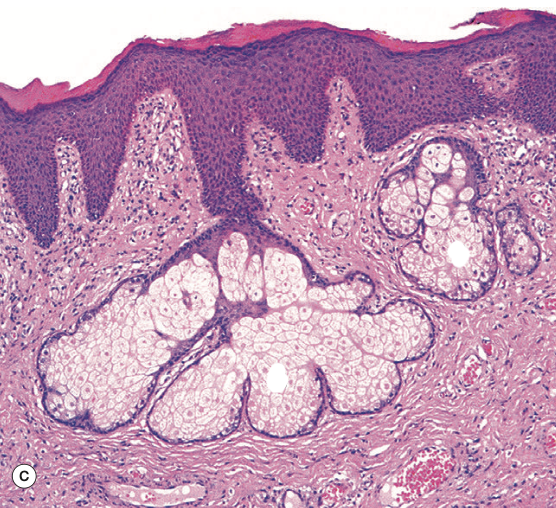

Identify the Structure in the middle

Sebaceous Gland

Identify the Structure on the L and R

Identify the Structure

Sebaceous Glands